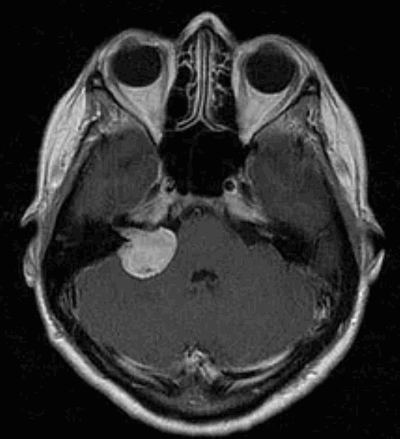

Вестибулярная шваннома (невринома VIII нерва, акустическая невринома) представляет собой доброкачественное новообразование, возникающее из шванновских клеток вестибулярной порции VIII нерва.

Наиболее информативным методом выявления вестибулярных шванном является МРТ головного мозга с контрастным усилением в режиме Т1 и Т2. Это исследование позволяет определить размеры опухоли, наличие перитуморозного отека, наличие признаков окклюзионной гидроцефалии, которая может быть следствием сдавления опухолью IV желудочка. Кроме этого МРТ позволяет провести дифференциальную диагностику с другими опухолями схожей локализации (чаще с менингиомой задней грани пирамиды височной кости). Еще одним стандартом диагностики является КТ в костном режиме. Независимо от снижения слуха стандартом является проведение аппаратной аудиографии.

Невринома слухового (вестибуло-кохлеарного) нерва составляет около 10% от всех опухолей внутричерепных нервов. Возникает чаще всего у женщин зрелого возраста, развивается под наметом мозжечка. Благодаря тому, что опухоль отделена капсулой, она не врастает в ткань мозга, а только оттесняет ее, иногда до существенной степени.

Чаще всего в этих случаях у пациентов можно наблюдать шум в ушах, звон, нарушение слуха, иногда паралич лицевого нерва. Если опухоль локализуется в мосто-мозжечковом углу, то это может привести к сдавлению водопровода мозга с дальнейшим развитием гидрацефально-гипертензийной симптоматики (головная боль, тошнота, рвота, застой глазного дна). К сожалению, пациенты довольно часто слишком поздно обращаются за квалифицированной помощью.

При проведении МРТ, СКТ исследований

Чаще всего обнаружение подобных опухолей не составляет особой сложности для диагноста и без внутривенного контрастного усиления. При внутривенном контрастном усилении можно детализировать локализацию самой опухоли, ответить на вопросы инвазии в соседние структуры, оценить кровоток образования и обзорно оценить отсутствие\наличие метастазов.